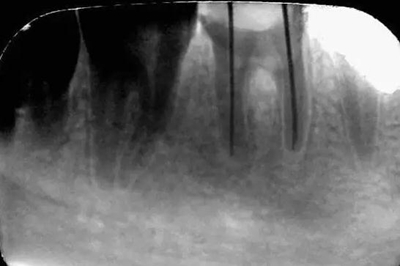

初尖銼,根測儀測量長度后拍照

初尖銼X光片:現(xiàn)在根測儀的準(zhǔn)確性的卻非常之高。

主尖銼:

主尖銼X光片: